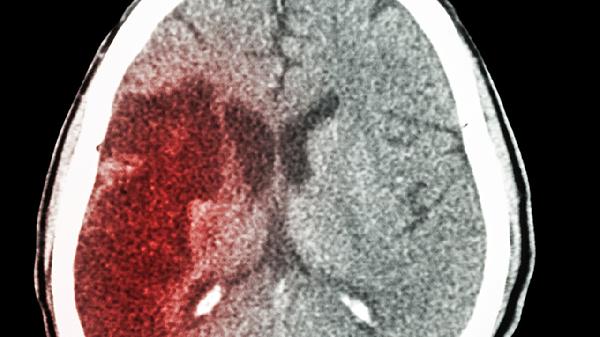

第三四脑出血通常比较严重,属于脑出血的一种类型,可能危及生命。

第三四脑出血是指发生在第三脑室和第四脑室附近的出血,这两个脑室是脑脊液循环的重要通路。出血可能导致脑脊液循环受阻,引起颅内压升高,严重时可能压迫脑干等重要结构。常见的症状包括剧烈头痛、呕吐、意识障碍、肢体无力等。出血量、出血速度以及是否及时治疗都会影响严重程度。如果出血量小且得到及时控制,预后可能相对较好;但如果出血量大或压迫关键部位,可能导致长期神经功能缺损甚至死亡。治疗上通常需要绝对卧床、控制血压、降低颅内压,必要时进行手术清除血肿。康复期需要长期随访和神经功能康复训练。